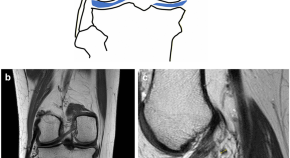

Artificial Intelligence-Powered Clinical Decision Support and Simulation Platform for Radiology Trainee Education